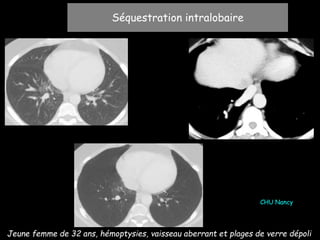

Jeune femme de 32 ans, hémoptysies, vaisseau aberrant et plages de verre dépoli

CHU Nancy